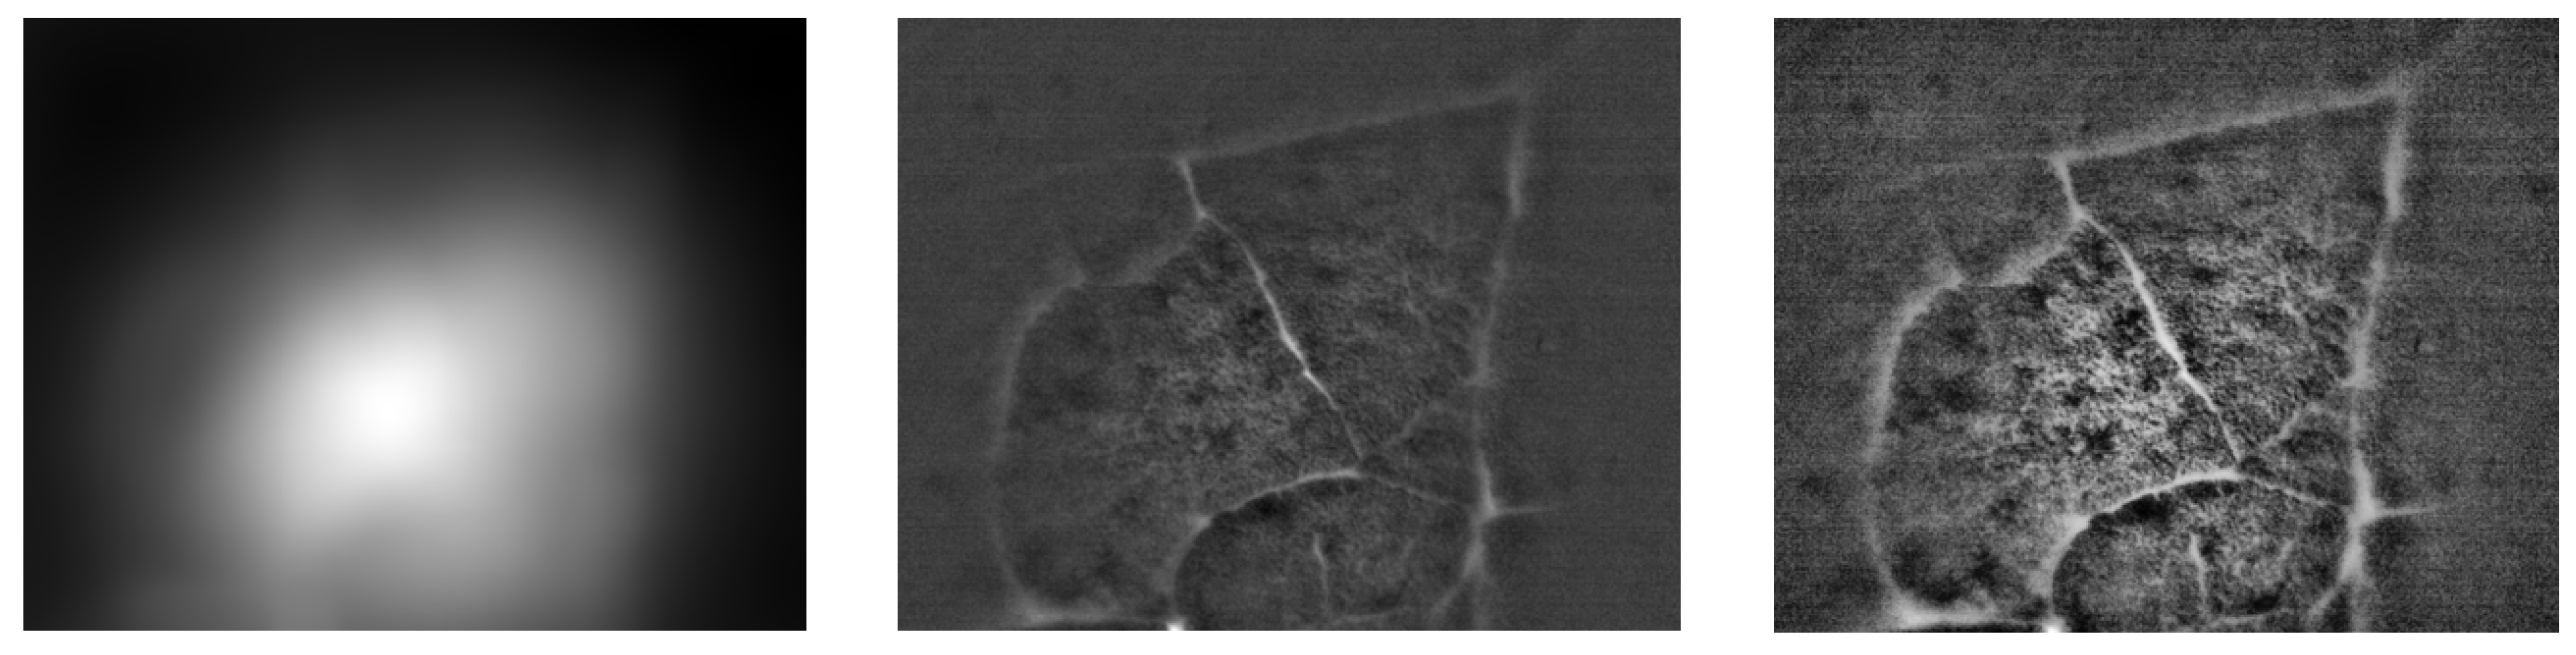

We performed basic image processing of the image acquired in a direct view setup. Due to strong non-uniform illumination and noise level in the acquired image I , we proposed a simple additive model for image processing. The corrected image I c o r r is computed as: I c o r r = I f i l t e r e d I * h , where I f i l t e r e d is the median filtered image with 3×3 kernel and h is a square averaging kernel with size 101 pixels. An example of this processing is shown in Figure 8. The corrected image contains more visible structures, particularly the alveoli borders and the structures within. Next processing step might involve appropriate histogram adjustment. Here we applied the contrast limited adaptive histogram equalization Pizer (1977), Tawfik (2024) in order to show the effect on corrected image.

Figure 8. Estimation of non-uniform illumination field (left), corrected image (middle) and image with adaptive histogram correction (right). The images are cropped in order to remove the border effect caused by image filtering. The original image is shown in Figure 7 left.